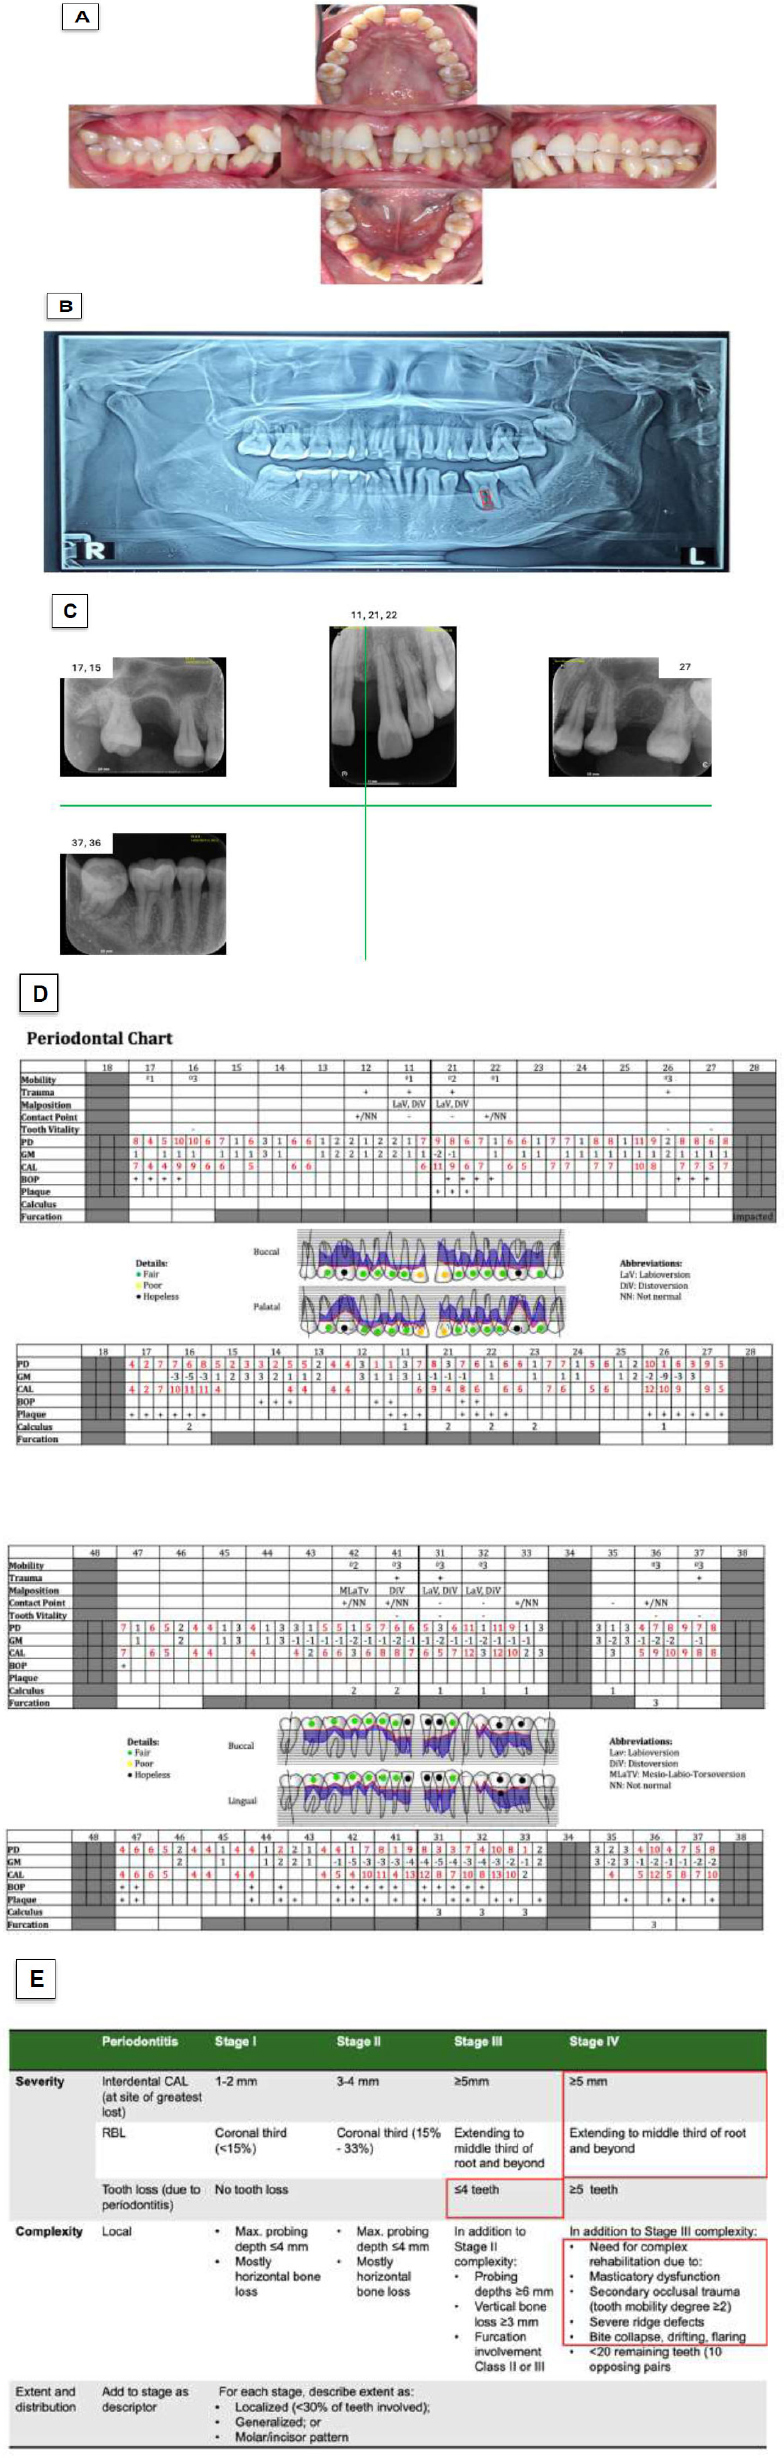

[Electronic Publication Date: November 22, 2025]Zahra Molaei, Paria Motahari and Fatemeh Sobhanifar